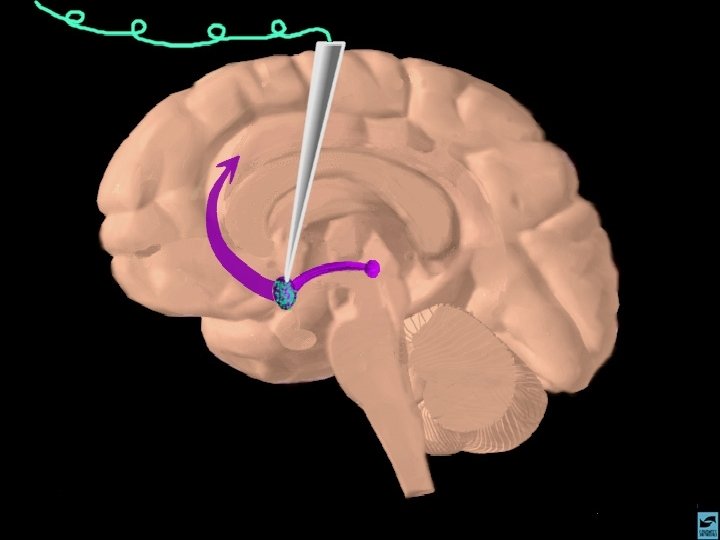

ANFETAMINAS E COCAÍNA EFEITOS CEREBRAIS: ATIVA OS SISTEMAS DOPAMINÉRGOS MESOLÍMBICOS E MESOCORTICAIS, INIBINDO A RECAPTAÇÃO DE DOPAMINA NOS TERMINAIS SINÁPTICOS E PROMOVENDO SUA LIBERAÇÃO NAS SINAPSES.